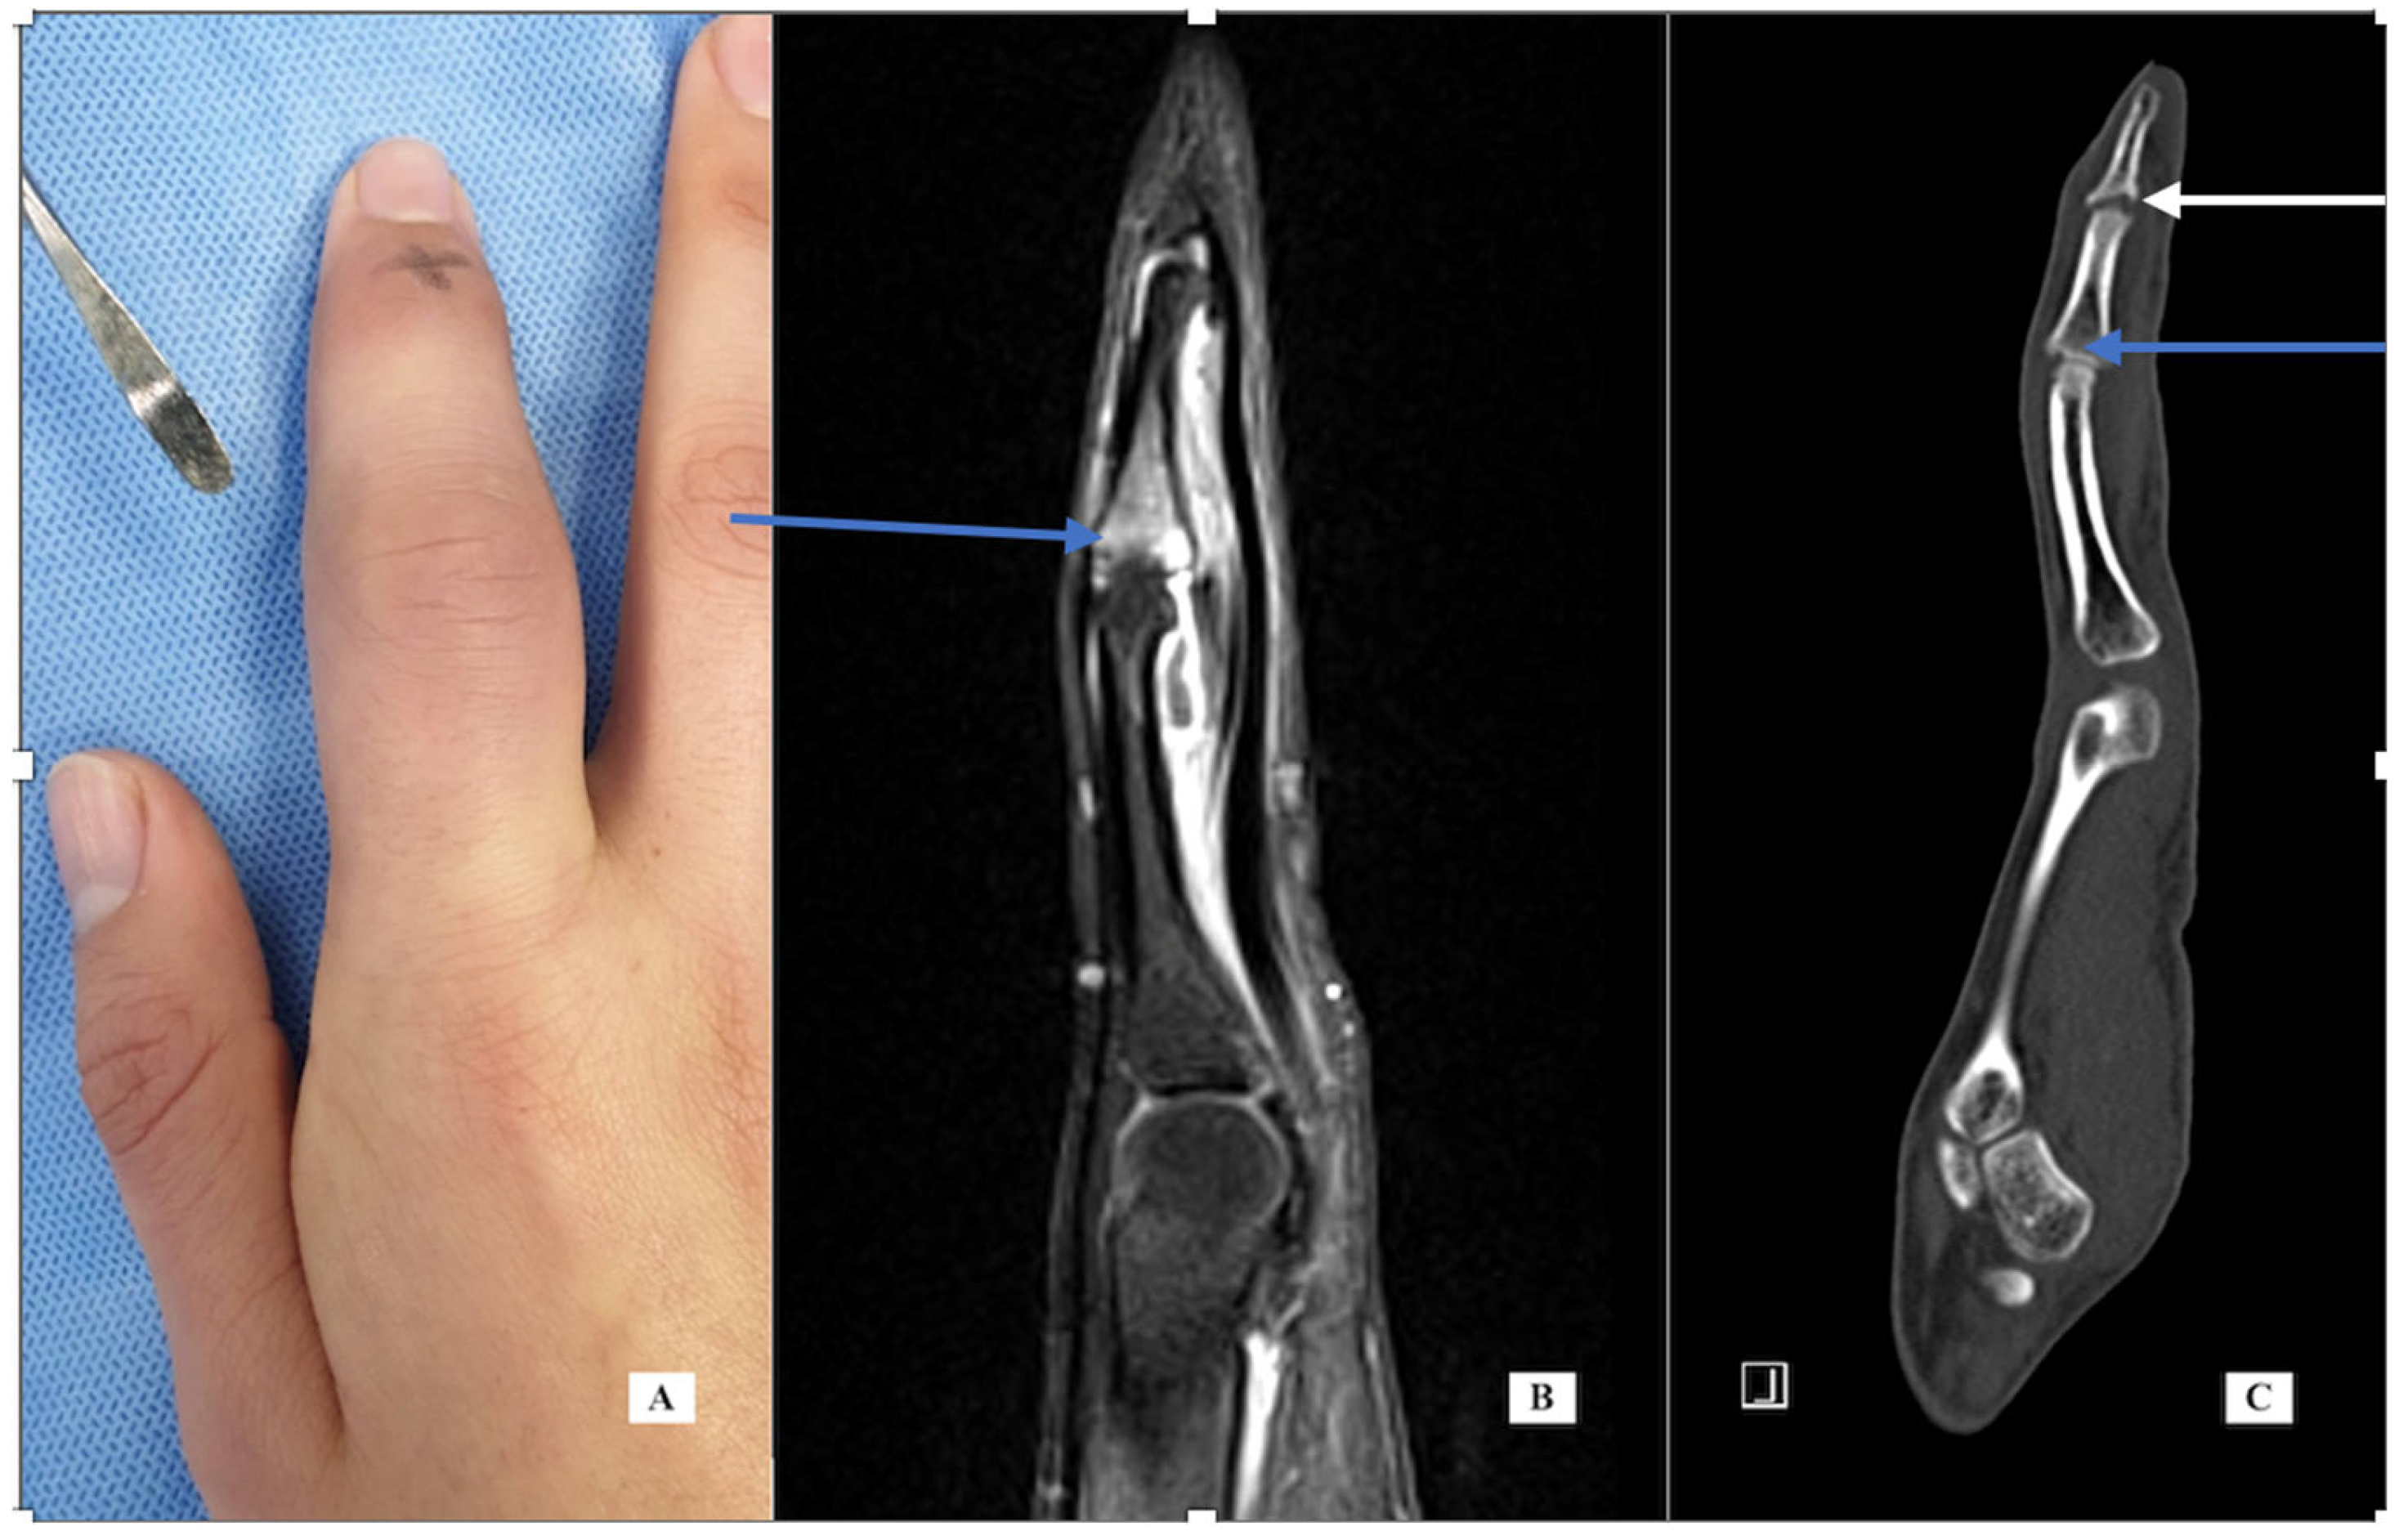

Case 4: A 12-year-old female presented with a 2-month history of right F4 PIP pain and stiffness. At the time of her presentation in January 2021, she had moderate swelling of her finger, mild local warmth, no erythema, PIP motion of 25 to 70 degrees, and local tenderness. X-rays showed a periosteal reaction of the distal P1 (Figure 3, left). Labs for inflammation were normal. The MRI scan (Figure 3, center, T1 with fat suppression) showed bone marrow edema enhancement, synovitis of the PIP joint, tenosynovitis of flexor and extensor tendons, and erosion irregularity of the volar distal cortex under the P1 condyle. The report noted that the images were consistent with osteomyelitis. She was referred to a pediatric rheumatologist for evaluation. His presumed diagnosis after evaluation was inflammatory or infectious disease. He recommended additional labs including serology for hepatitis, creatine phosphokinase (CPK), anti-nuclear antibody (ANA) using immunofluorescence assay (IFA) methodology, and urinalysis, all of which were negative.

At that point, the images were reviewed with an orthopedic tumor specialist (AP), who suggested evaluation with a CT scan. The images (Figure 3, sagittal view, right) showed a small lucent cortical lesion 4 mm in length with central calcification and a periosteal reaction of the proximal phalanx consistent with osteoid osteoma (OO). She denied increased symptoms at night or pain relief with NSAIDs. She was taken to surgery using a volar approach and the lesion was treated with curettage and with local burring, but no additional adjuvant treatment. Pathology was consistent with OO and the margins were clear. Her pain resolved and the swelling and motion improved. At her last appointment, her X-rays had normalized.

Case-specific comment: The plain X-rays did not reveal the diagnosis that became apparent only with the CT scan. In retrospect, the periosteal reaction seen on the plain X-rays was a result of the osteoid osteoma in the distal metaphysis. Since there is no periosteum in the metaphysis, the inflammatory reaction stimulated periosteal new bone formation more proximally along the diaphysis. This periosteal new bone resorbed after removal of the nidus. Typically, the nidus is well-seen in MRI, but perhaps because of the small lesion and the resolution of the images, the diagnosis was not made via MRI but seen clearly on the CT scan.

Figure 3. Case 4—X-ray lateral of the finger (A) demonstrating cortical thickening; MRI sagittal of the finger (B) demonstrating bone marrow edema distal P1, irregularity of the distal cortex (blue arrow) and generalized soft tissue swelling; CT sagittal of the finger (C) demonstrating lucency with a central calcification consistent with nidus.